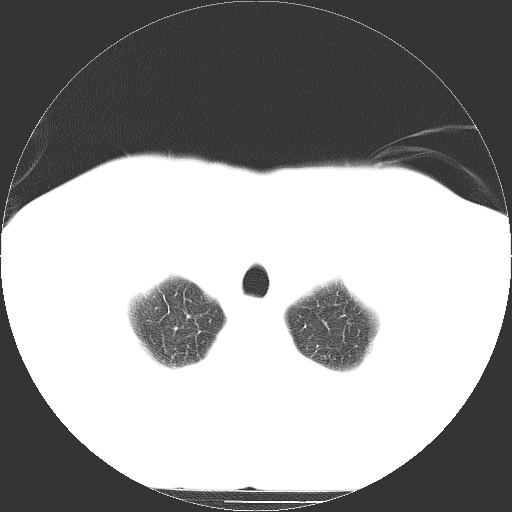

标题: CT21804:男,65岁,咳嗽、咳痰、发热5天。 [打印本页]

男,65岁,咳嗽、咳痰、发热5天。

慢支 肺间质纤维化合并感染!

支气管扩张合并感染,胸膜肥厚

考虑慢支并感染,肺间质纤维化。

两肺间质性炎症并感染

慢支,肺心病

支持慢性支气管炎伴感染,双侧少量胸腔积液.

两肺间质纤维化,支扩合并感染,双侧胸腔积液

感染,肺间质纤维化。

慢支 肺间质纤维化合并感染

支持慢性支气管、肺间质纤维化合并感染。

慢性支气管炎并感染,支扩,双侧少量胸腔积液.